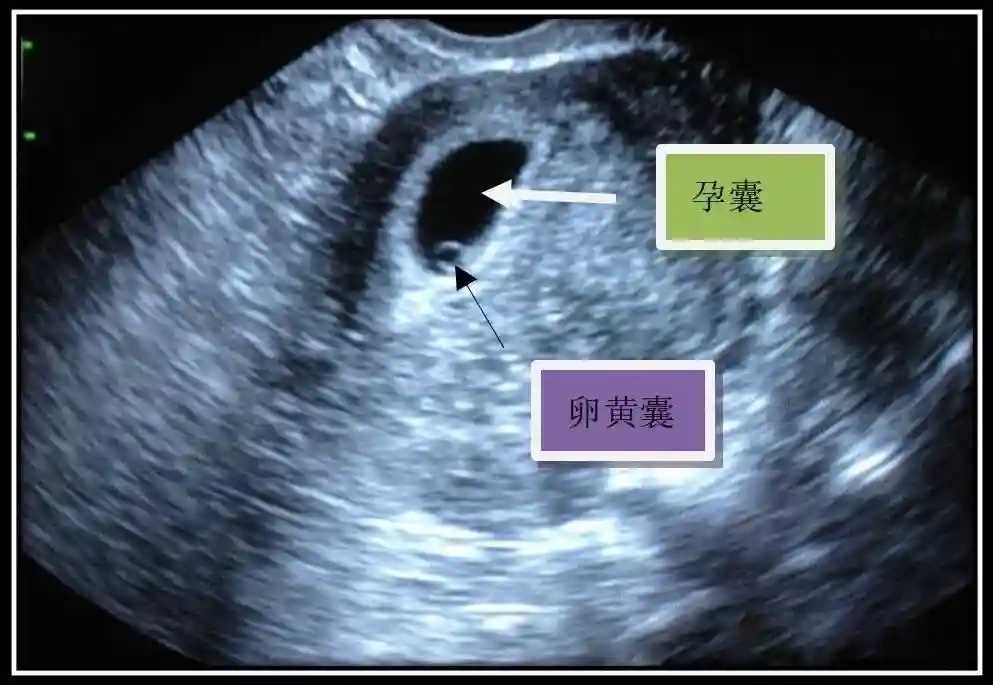

2️⃣卵黄囊:是妊娠囊内第一个解剖结构,直径<7mm。表现为小环状,中央为无回声,囊壁薄,内透声好。卵黄囊位于胚胎旁胚外体腔内。卵黄囊通常在孕5-6周时出现,5-10周稳步增长,一般不超过7mm,至12周消失。妊娠囊的大小与卵黄囊之间有一定关系,妊娠囊平均直径> 8 mm 时,经阴道超声均应显示卵黄囊,妊娠囊平均直径> 18 mm 时,经腹超声均应显示卵黄囊。

3️⃣胚胎:胚胎通常在6-7周时可以为超声显示,起初为胎芽,表现为卵黄囊一侧局部组织增厚,达到1 -2 mm 时才有可能为超声测量出来。达4-5mm时可见胎心搏动,相应孕周为6-6.5周,妊娠囊大小为13-18mm。胚芽长度≥7㎜时仍未见心管搏动,提示胚胎停止发育。胚胎的出现和妊娠囊直径的关系:妊娠囊直径> 16 mm 时,经阴道超声应显示胚胎。妊娠囊直径> 25 mm 时,经腹超声均应显示胚胎。